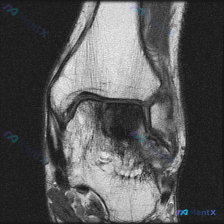

这是一张单幅膝关节矢状位T1加权MRI影像,问题是观察图像中是否存在软骨异常。

影像本身特点:图像有明显噪声(颗粒感重),对比度一般,解剖结构轮廓可辨认,但精细细节分辨率受限,属于质量不佳的单幅影像。